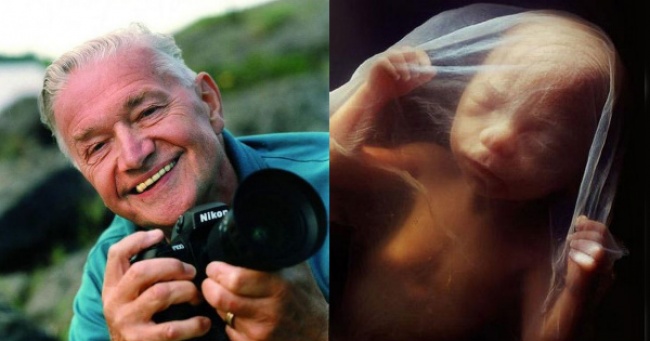

13 8-week-old embryo. The fetus is well protected in the fetal sac